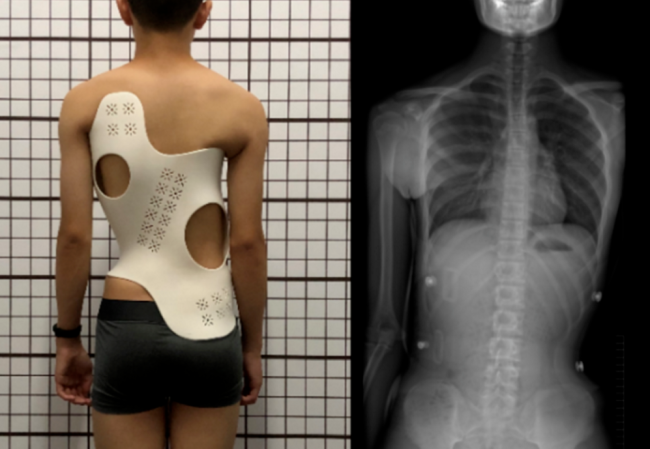

医疗器械行业的3D扫描服务

在医疗器械行业,精密零件的设计和制造对于设备的性能和安全性至关重要。3D扫描技术已经成为这一行业中不可或缺的工…